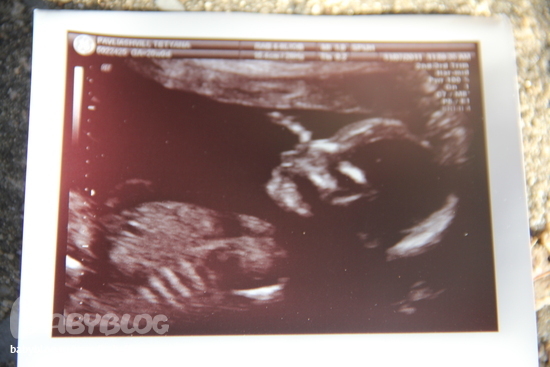

О хорошемИтак ходили сегодня на узи с мужем и доченькой)) .главное конечно то, что все у нас хорошо, дете здоровое и крепкое, вес приблизительно 400 грамм, сердечко в норме, внутренности в норме, пальчики-ручки-ножки все в норме)Устраивал там нам показательное выступление, не секунды покоя, ноги выше головы, пальцы сосем, язык показываем. кароче насмеялись там с мужем и врачихой)

Вобщем когда мне показали фото, того самого причинного места, я и ахнула)) врачиха поняла все и говорит - да.да папочка, я на Вашем месте бы гордилась сыном))) муж покраснел, но сидит такой гордый, грудь вперед)) Вобщем и наконец-то фото нашего сыночки)

на то самое место указывают стрелочки))